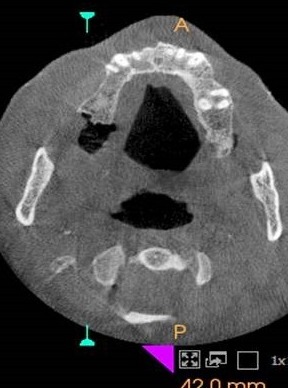

INTRAORAL PICTURE CBCT APPEARANCE HISTOPATHOLOGICAL PICTURE